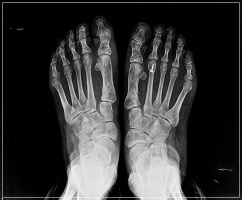

무지외반증 여부의 진단은 시진과 촉진(발가락 모양, 굳은살 등)으로 가능하지만 치료 방침을 결정하기 위해서는 방사선 검사가 필요합니다. 뼈와 뼈가 이루는 각도, 관절의 변형과 염증, 운동 범위 등을 측정합니다.